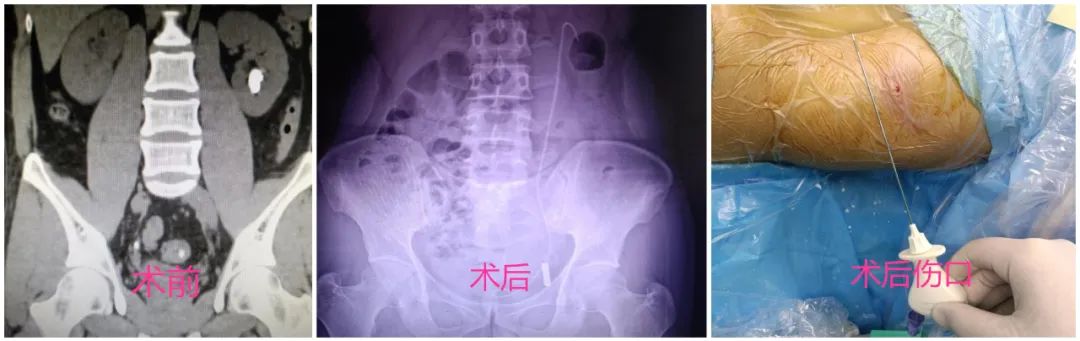

近日,漳州市中醫(yī)院在漳州地區(qū)率先開展超微通道可視腎鏡聯(lián)合輸尿管軟鏡腎下盞結(jié)石碎石取石術(shù),目前兩位患者已康復(fù)出院!

兩例患者術(shù)前檢查時(shí)發(fā)現(xiàn)腎盂漏斗角(IPA)均小于30°!腎盂漏斗角(IPA)大小是影響輸尿管軟鏡碎石術(shù)成功與否的關(guān)鍵,正常IPA范圍35°—109° ,綜合資料顯示當(dāng) IPA >30°時(shí),輸尿管軟鏡碎石成功率為92.5%,而 IPA <30°時(shí)成功率僅為38.4%。

鑒于兩例患者腎盂漏斗角(IPA)均小于30°,陳惠新泌尿外科團(tuán)隊(duì)在廈大附一院泌尿外科陳斌教授指導(dǎo)下,采用目前國際上最先進(jìn)、極致微創(chuàng)的超微通道可視腎鏡配合輸尿管軟鏡鈥激光碎石技術(shù),成功為兩位患者清除腎結(jié)石。

小知識:可視腎鏡又稱針狀腎鏡,直徑僅1.4毫米,具有穿刺、攝像、碎石功能,是目前全球直徑最小的腎鏡,也是唯一“長眼睛”的針狀腎鏡。它具有可視光纖、激光碎石以及進(jìn)水口3條通道,其中可視光纖直徑僅0.7毫米,可實(shí)時(shí)傳輸高清影像,幫助醫(yī)生穿刺時(shí)避開血管直達(dá)病灶,發(fā)現(xiàn)結(jié)石后,利用激光把結(jié)石擊碎,能極大提升腎結(jié)石微創(chuàng)手術(shù)的精準(zhǔn)性,降低對人體的損傷,是目前世界上經(jīng)皮腎鏡碎石術(shù)(PCNL)的一種“最微創(chuàng)”形式,其以創(chuàng)傷小、療效高、恢復(fù)快等優(yōu)點(diǎn)備受全球泌尿結(jié)石領(lǐng)域?qū)<业那嗖A。

手術(shù)的成功開展標(biāo)志著我院泌尿系結(jié)石的微創(chuàng)治療水平又上了一個(gè)新臺階,相信隨著此項(xiàng)技術(shù)的進(jìn)一步推廣,會(huì)讓更多的泌尿系結(jié)石患者獲益。